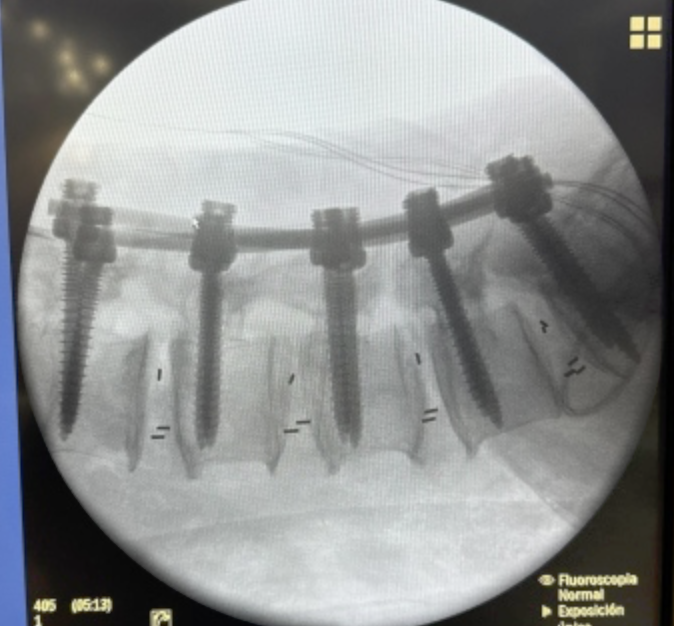

CIRUGIAS

PREPARACION DEL PACIENTE

RESULTADOS